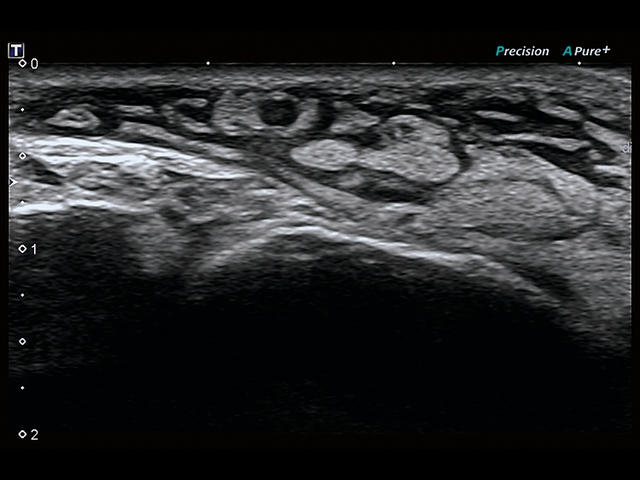

Обновленная версия легендарного УЗ-сканера. Стационарный аппарат экспертного класса Aplio 500 Toshiba NEW, визуализирует анатомические структуры в высоком разрешении. Модель позволяет выявить микрокальцификаты, новообразования, нарушения в работе сердца, сосудов и мышц. Присутствует функция виртуальной эндоскопии, 4D-сканирования, эластометрии тканей, УЗИ с контрастированием. За повышение качества изображения отвечают технологии ApliPure и Superb Microvascular Imaging. Первая задействует возможности пространственного и частотного кодирования, формирует цельный визуальный ряд с сохранением клинических маркеров. Вторая улучшает отображение микрососудистого русла, используя доплеровский эффект. Модель оснащена 21-дюймовым монитором, имеет 4 активных порта. Возможно подключение педиатрических, интраоперационных, лапароскопических и чреспищеводных датчиков.

• D-THI.Режим дифференцированной тканевой гармоники, повышающий качество визуализации глубоко расположенных тканей. Получаемое изображение отличается высокой четкостью, не содержит дефектов в виде «заснеженных» и размытых участков.

• SMI. Опция, упрощающая визуализацию микроциркуляторного русла. С ее помощью обследуются сосуды с низкой интенсивностью кровотока, изучаются наиболее тонкие структуры. SMI упрощает диагностику новообразований, минимизирует вероятность ошибки.